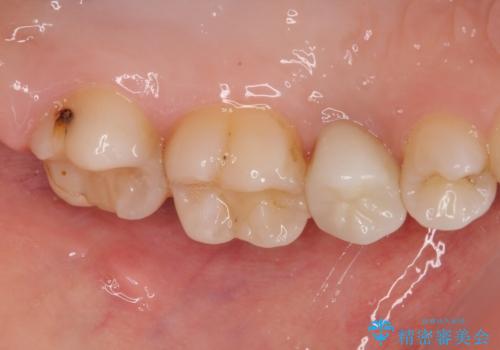

- 左上が虫歯になった気がするとのことで来院された患者様です。

左上の七番目と六番目の歯と歯が接するところに虫歯をレントゲン上で確認できました。

噛み合わせが強く、以前にも当院で右上でゴールドインレーにより治療をされていたのでゴールドインレーにて治療しました。

拡大鏡視野下で、虫歯の除去を行い、ゴールドインレーに適した形に整えました。